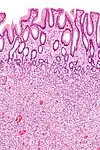

| Type de polype | Apparence histologique | Risque de malignité | Coupe histologique | Syndromes | |

|---|---|---|---|---|---|

| Hyperplasique | Cryptes dentées non-ramifiées | Non | ![]() |

Hyperplasique polypose syndrome | |

| Adénome dentelé sessile | Semblable à hyperplasique avec hyperserration, bases des cryptes dilatées/ramifiées, des cellules de mucine apparents à la base des cryptes | Oui | ![]() |

||

| Inflammatoire | Muqueuse/sous-muqueuse élevées avec inflammation | Si développement d'une dysplasie | Maladies inflammatoires chroniques intestinales, ulcères, infections, prolapsus muqueux | ||

| Adénome tubulaire (villositaire, tubulovilleux) | Glandes tubulaires avec des noyaux allongés (au moins à faible teneur atypie) | Oui | ![]() |

| Adénome dentelé traditionnel | Cryptes dentelées, souvent une structure villeuse, avec atypie cytologique, des cellules éosinophiles | Oui | ![]() |

| Polype de Peutz-Jeghers | Faisceaux musculaires lisses entre l'épithélium non-néoplasique, apparence d'« arbre de Noël » | Non | ![]() |

Syndrome de Peutz-Jeghers | |

| Polype juvénile | Glandes kystiques dilatées avec la lamina propria élargie | Non intrinsèquement, peut développer une dysplasie | ![]() |

Syndrome de polypose juvénile, polypes identiques que dans le syndrome de Cronkhite-Canada | |

| Polype hamartomateux | Variable ; polype classique légèrement fibreux avec la muqueuse désorganisée et écartement des muscularis mucosae ; aussi inflammatoire, juvénile, lipome, ganglioneurome, lymphoïde | Non | Maladie de Cowden | ||

| Polype fibroïde inflammatoire | Cellules en fuseau avec des amas concentriques de cellules fusiformes autour des vaisseaux sanguins et l'inflammation riche en éosinophiles | Non | ![]() |